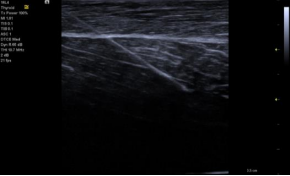

Needle Visualization 穿刺增强

‒先进的图像后处理提高了穿刺针的显示

‒ 支持多个角度平面内穿刺针增强显示角度最大可达 35°

‒ 适用于所有线阵探头